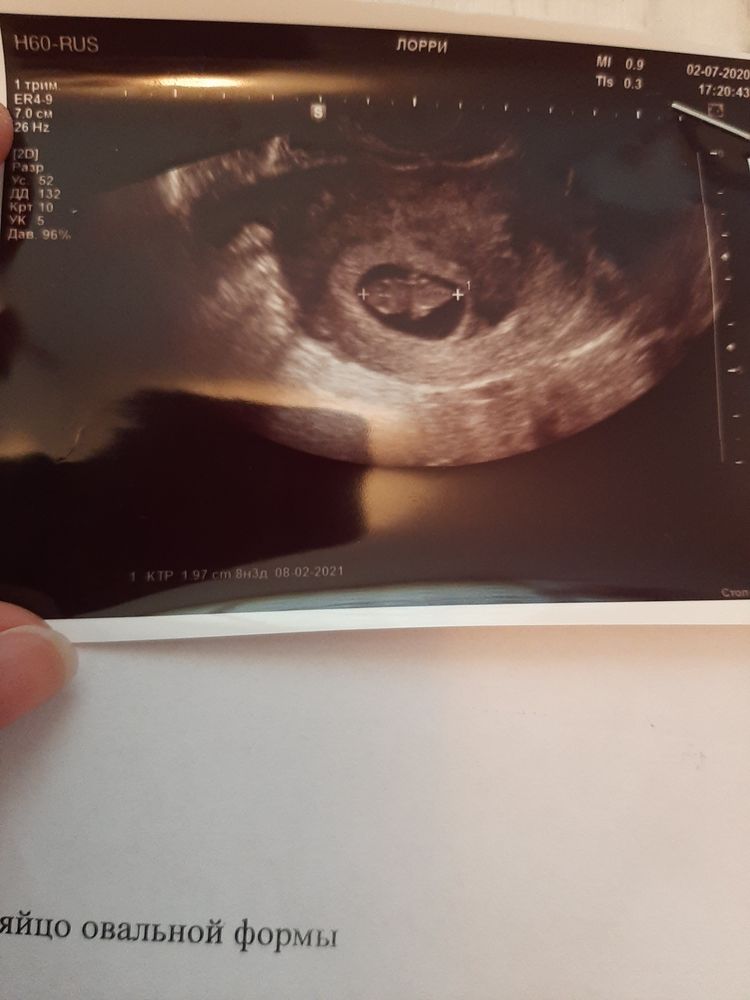

Я ходила на узи в 7 недель, и сходила сегодня в 9 недель, и мне ни разу не написали размер ПЯ.

Меня это смутило, но в прошлый раз по УЗИ было видно, что оно большое, а ктр всего лишь 5,5 мм был.

А тут смотрю я на экран, кроха так выросла😍🙏 Пусть растет😍 на 14 мм выросли, все четко, меня все устраивает😅

А вот плодное яйцо как будто не выросло.. Малыш прямо полностью его заполняет.

Жаль, что не сравнить размеры..

И теперь немного страшно, ПЯ ведь тоже должно расти... Скорее всего оно выросло, просто не зная размеры, так кажется 🤷♀️😒

СБ 144 удара, это ведь нормально? Просто где-то читала, что с 7 по 10 неделю от 160 ударов, а потом на спад идет.. но Узист ничего не сказала🤷♀️